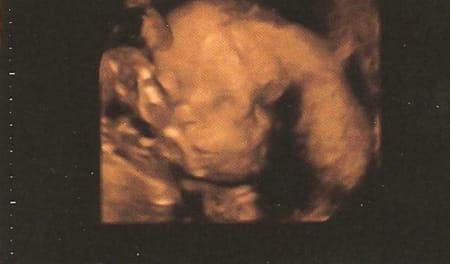

BB2 en préparation

Occasion :

Date :

09-07-2014

Lieu :

Naissance prévu début Juillet 2014